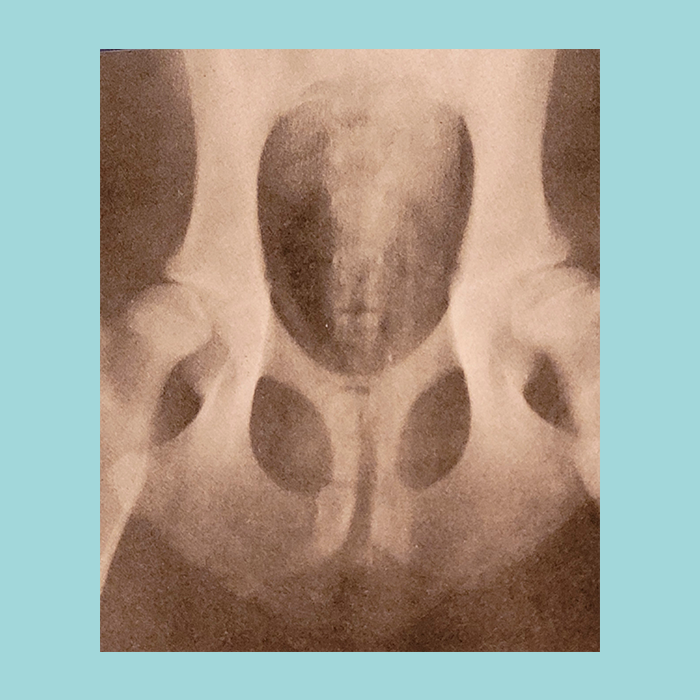

2. Тазобедренный сустав. Фото № 1. Это сустав соединяющий бедренную кость с тазовыми костями. Значит мы будем говорить только об отклонении от нормы и нарушении развития тазобедренных суставов.

Фото №1

8. Не советую подвергать щенков моложе 12 месяцев рентгенографии с укладкой по спец методике для определения ТБС. Это может закончится травмами, совершенно неоправданными для малыша. Все связки, фасции и мышцы у малыша еще не сформировались. Укладка, см. фото №2, может повредить и мышцы, и связки, и фасции, и даже позвоночник.

фото № 2